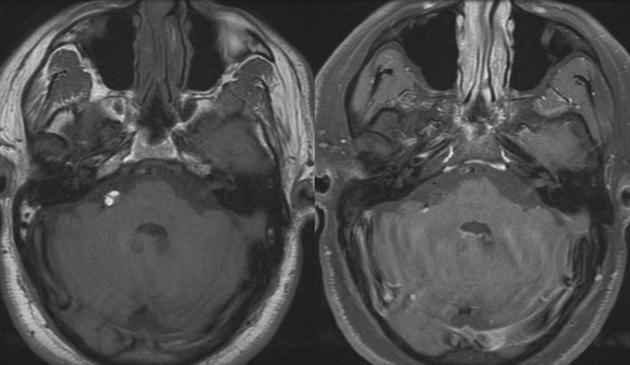

Diagnosis?

Chiari II.

Findings on antenatal ultrasound: banana cerebellum sign, lemon sign.